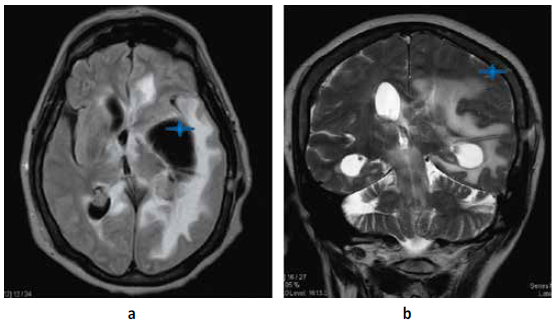

Paciente mujer de 73 años natural de Lima Perú con tiempo de enfermedad de 2 meses caracterizado por trastorno del sensorio, vómitos, cefalea y alteración de marcha; al examen físico neurológico se evidencia desorientación, hemiparesia derecha a 2/5 (Escala de Daniels), Babinsky derecho (+) Hoffmann derecho (+), parálisis facial central izquierda. motivo por el cual se realiza resonancia magnética cerebral (RMN) con contraste (c/c) evidenciando lesiones de aspecto nodular que comprometen ventrículos laterales, con extensión al III Y IV ventrículo, condicionando edema perilesional e hidrocefalia con signos de efecto hipertensivo Figura N°1; Se decide manejo quirúrgico de emergencia colocación de un sistema de derivación ventrículo peritoneal bilateral Figura N°2 y N°3. Ya con el paso de los días y mejoría del cuadro de hipertensión endocraneana resuelto se decide realizar biopsia guiada por estereotaxia obteniéndose por resultado de anatomía patológica proceso linfoproliferativo de células redondas atípicas correspondientes a células B maduras. Motivo por el cual se decide tratamiento oncológico con uso de radioterapia (10 sesiones) y corticoides que se realiza durante 3 meses; Es dada de alta con mejoría clínica. Al cabo de 4 meses el paciente acude para su control, se realiza tomografía cerebral (TEM) sin contraste (SC)Figura N°3evidenciando ausencia casi total de la tumoración y mejoría de los síntomas.